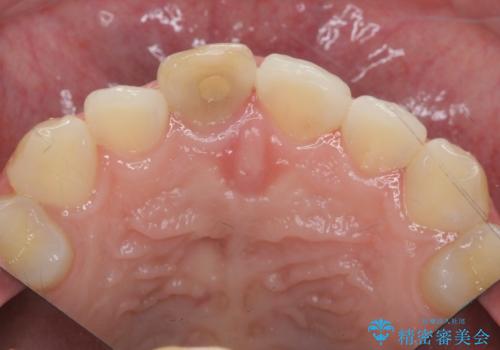

歯ぐきにできものができた 前歯の色調改善

- 歯ぐきに、にきびのようなものができ治らない、と治療を希望され来院されました。

歯髄の検査、X線検査より神経の失活が確認されたので、根管治療・ファイバーコア築盛 ・ジルコニアクラウンの製作、と治療を進めます。

根管治療を行ったことで、歯ぐきのできものは治癒し再発をしなくなりました。